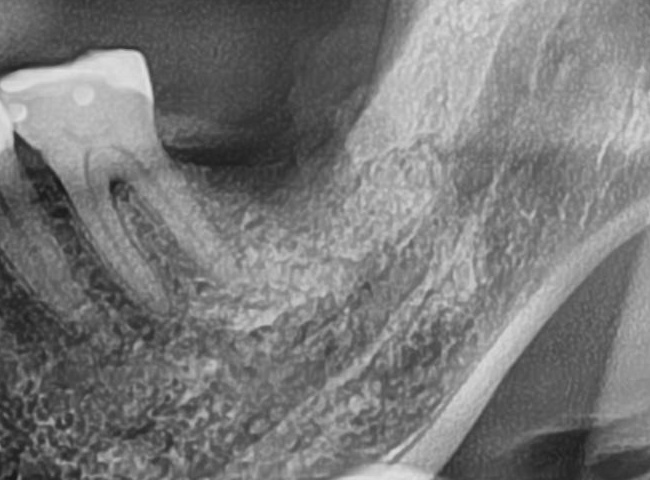

ドリルの先端を細い物から徐々に大きい物に変えながら、植立するインプラント体のネジの部分を除いた胴の部分の太さに合わせた大きさの穴を開けていきます。

開けた穴に、専用道具を使ってネジを締めるように長さ2センチ程のインプラントを骨に埋め込んでいきます。